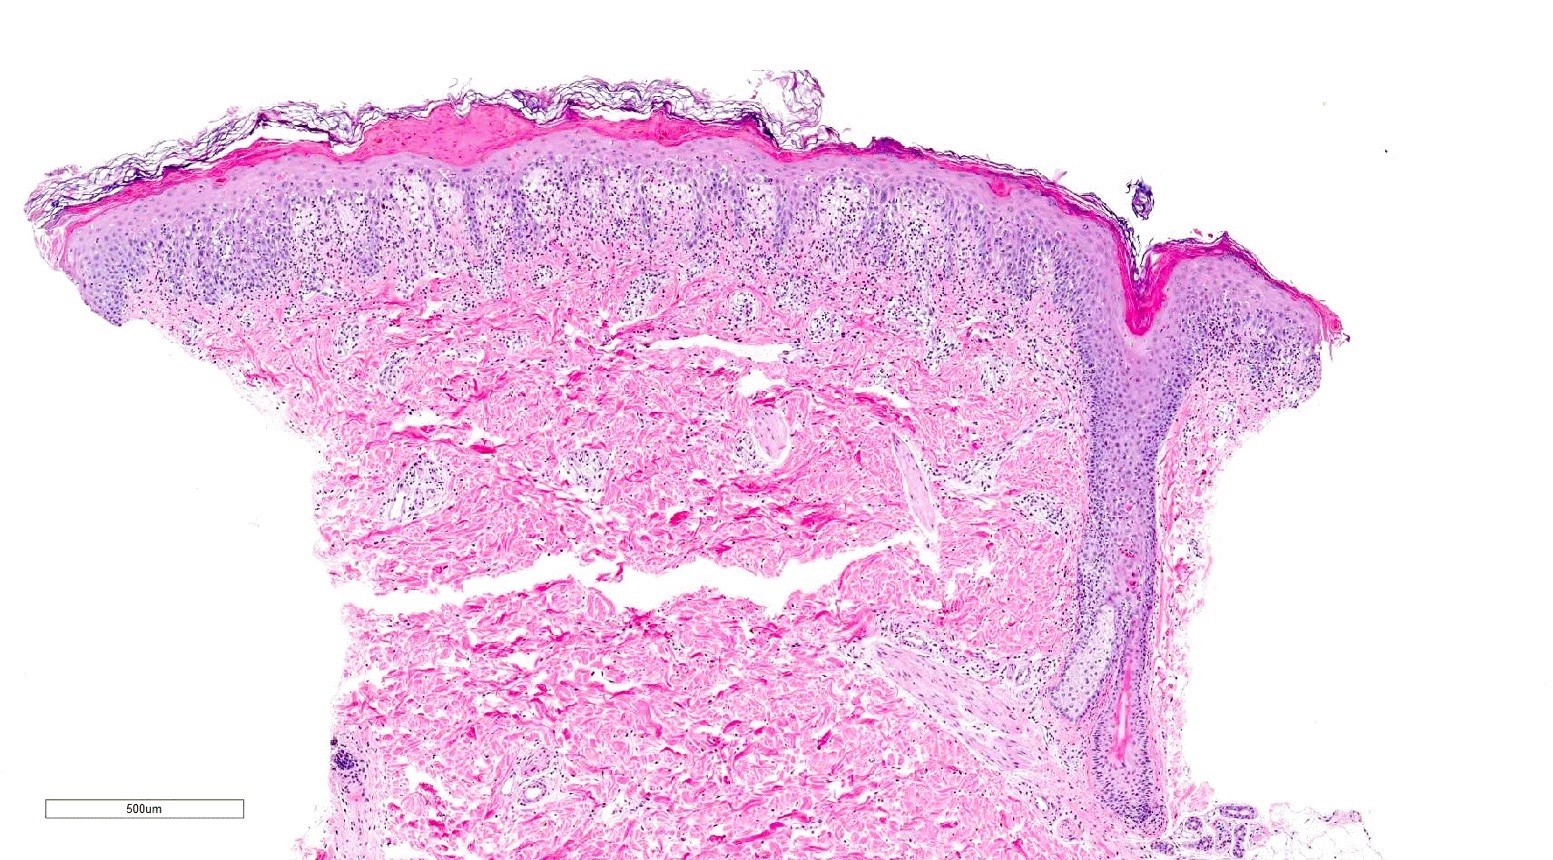

Microscopic (histologic) description

- Chronic GVHD (Biol Blood Marrow Transplant 2015;21:589, Patterson: Weedon's Skin Pathology, 4th Edition, 2015)

- Chronic lichenoid GVHD

- Acanthosis, orthohyperkeratosis, parakeratosis with hypergranulosis

- Underlying band-like lymphocytic infiltrate with basal layer vacuolization and apoptotic keratinocytes

- Periadnexal inflammation can be present

- May be difficult to distinguish from lichen planus without clinicopathologic correlation; satellite cell necrosis is the most helpful clue in GVHD biopsies to distinguish it from lichen planus

- Chronic lichenoid GVHD

Microscopic (histologic) images

Contributed by Silvija P. Gottesman, M.D. and Ohoud Aljarbou, M.D.